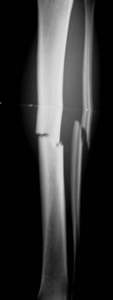

Unterschenkelfraktur mit schwerem Weichteilschaden

nach Quetschung. Zunächst wird die Fraktur mit dem Fixateur

(Monotube) stabilisiert. Erst nach Abschwellen der Weichteile ist

der Verfahrenswechsel zum Verriegelungsnagel möglich. Die primäre

Nagelung ist auch mit einem sogenannten ungebohrten Nagel zu riskant.